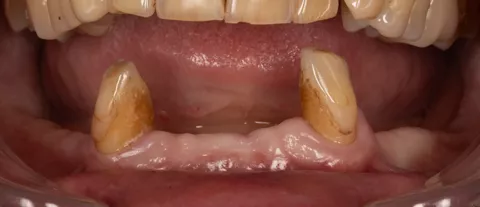

2c. Situation in the mandible: thin alveolar crest and residual teeth 33 and 43.

2c